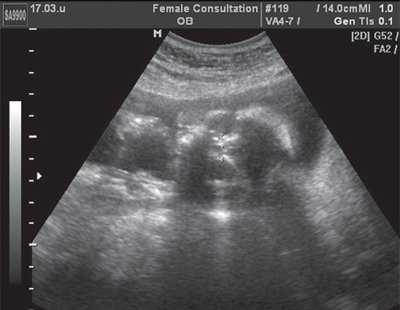

На первый взгляд, эта методика не очень сложна, однако правильно провести все этапы объемной реконструкции можно только при высоком качестве первично полученного объема. Даже при отсутствии патологии легких существует много факторов, затрудняющих визуализацию этого органа и влияющих на качество объемной информации. Прежде всего это срок беременности. До 32 нед неудачными для дальнейшей обработки являются 3-7% от всех сохраненных объемов, тогда как после этого срока - около 30%. Кроме того, к таким факторам относятся маловодие, плохая визуализация плода при ожирении пациентки, неудобное (например, поперечное) положение плода. Диафрагмальная грыжа сама по себе резко ухудшает визуализацию легких в связи с их компрессией (рис. 2) [3].

Рис. 2. Измерение объема контралатерального легкого при левосторонней диафрагмальной грыже. Тень от ребер мешает визуализации границ компрессированного легкого.